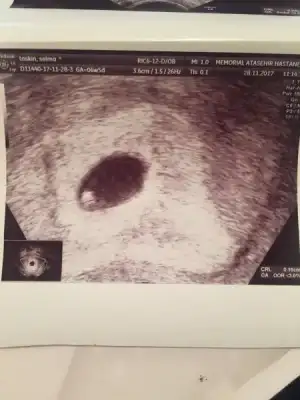

Canım benim ya yazdklarn anlattklarn çok zor Bliyorm o yıkımı. Rabbim inşallah bdaha o acıyı yaşatmaz inşallah en yakın zamanda Rabbim sana bir melek gönderir. Rabbim yardmcn olsn kendne iyi bakMerhaba anneler. Bu mesajı cok zor bir psikolojide yazıyorum. En son Perşembe günü kanama alanı azaldı ve bebeğim 2cm olmuş diye yazmıştım ve mutluluğumu paylaşmıştım. Ne yazikki aynı gece inanilmaz bir ağrı ile uyandım ve anlatamayacağım kadar çok kanamam oldu, hemen acile gittik ve yatış yapıldı. Sabaha kadar kanadım bir çok parçada düştü. Sabah ultrason kontrolünde gündüz çok sağlıklı,kalp atışı çok iyi ve görüntüsü muhteşem olan bebeğim kesesi ile birlikte yok olmuştu. Düşük yapmışım. Kürtaj olmadım bir hafta sonra kontrole gidicem.4 gündür dünyadamıyım, yaşıyor muyum bilemiyorum. 5. Tüp bebek denememde ilk defa hamile kalmıştım. 20 gün az az kanamam vardı. Bir çok igne ve hap almama rağmen 8+3 Bebeğimi kayıp ettim. Şimdi tekrar sil baştan denemek ve acaba bir daha hamilelik şansını yakalayabilecek miyim diye düşünmek çok üzücü. Herşey Allahtan tabi. Ancak inanılmaz yıkım oldu. Psikolojimi nasıl düzelteceğimi bilemiyorum. Icimden hiç birşey yapmak gelmiyor. Sizleri de sıktım belki ama paylaşmak istedim. Dilerim hepiniz sağlıkla kucağınıza alırsınız bebeklerinizi. Sağlıkla güzel günler diliyorum hepinize. Hoşçakalın.